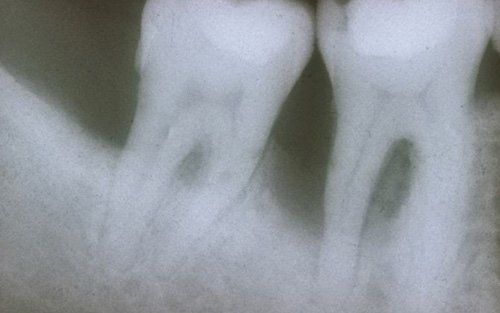

This treatment should be reserved for teeth that have irreversible pulp pathology (the nerve of the tooth) or an infection of the dental canals that has caused an abscess (acute apical periodontitis) or a granuloma (chronic apical periodontitis). While in the first two cases the tooth is very painful and the patient immediately seeks the dentist, the case of the chronic form is often silent, and therefore the patient may not notice anything for a medium to long period of time. In such conditions, it is only an X-ray image, taken during routine check-ups, that detects its presence. Root canal therapy can be completed by placing a latest-generation post inside the canal, as a means of retaining the material used for the reconstruction of the tooth. It will be up to the clinician to decide whether or not the restoration requires this additional anchoring system.